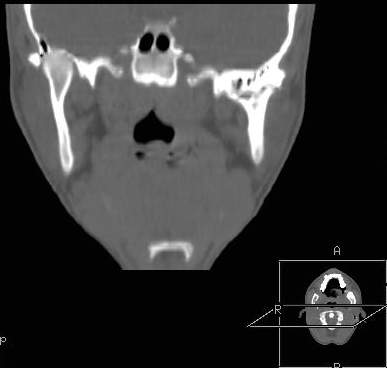

Пациент В., 13 лет. Диагноз: Костный анкилоз левого височно-нижнечелюстного сустава (ВНЧС), левосторонняя микрогения. Болеет с 2-х летнего возраста. Возможная причина развития анкилоза – воспалительный процесс (в первые 1,5 года жизни часто болел простудными заболеваниями, травму родители отрицают). В 3 и 5 лет проводилась редрессация – безуспешно.Прилагаются: ортопантомограмма, кадры СКТ с 3Д реконструкцией. Вопросы: определение тактики лечения – вид и сроки реконструктивно-пластической операции (этапов операции), а именно – неоартропластики и устранения микрогении, медикаментозная терапия в до- и послеоперационный период, ортодонтическое лечение.